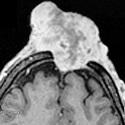

Darier Ferrand dermatofibrosarcoma of the scalp with frontal intracranial extension

Ali Akhaddar, Mohammed Lakouichmi

PAMJ. 2014; 18: 264. Published 30 July 2014